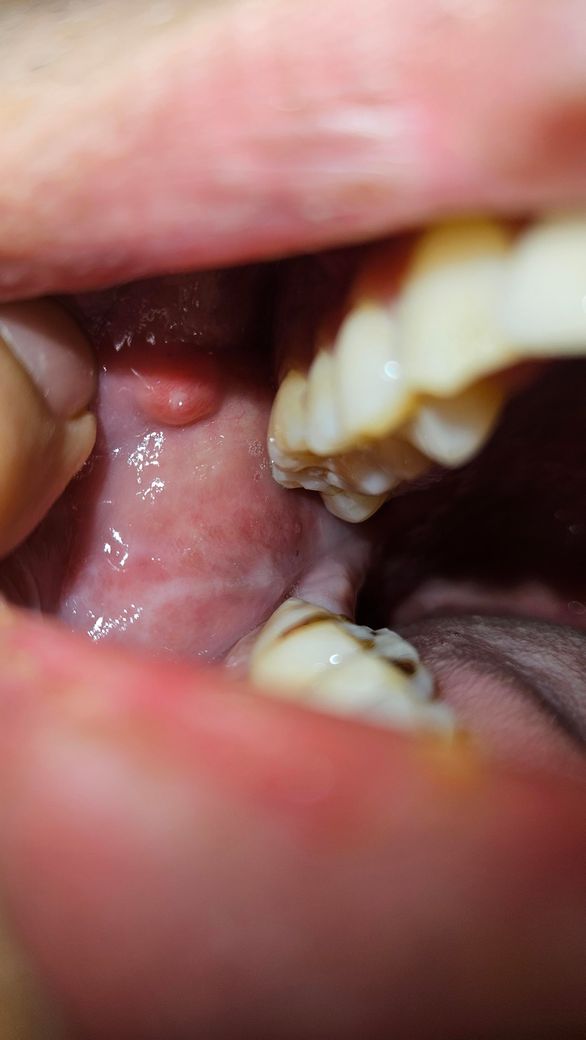

입안 볼살 염증(농양) 어느진료과에서 치료해야 되나요?

오늘 아침 자고 일어나니, 입안통증이 있어, 보니 우측 윗어금니 부분 볼살이 부어있었습니다. 이에 인근 치과에 급하게 방문하니, 목시클란정375mg 3일치 처방해주시면서 이후에도 통증이 있으면 내과나 이비인후과에 가보라고 하시더군요. 오늘 늦은오후에 다시 입안을 ㅂ느니 더 심해져서 노란농양이 생겼더군요(사진상 플래시로 노란 농양은 안보임). 이럴 경우 다음주 월요일에 다른 치과를 가야될지 아니면 이비인후과를 가야될지 고민되어 문의드립니다. 그리고 배농으로 입안 절개까지 고민해봐야 되는지 문의드립니다.

• 1번 째 사진